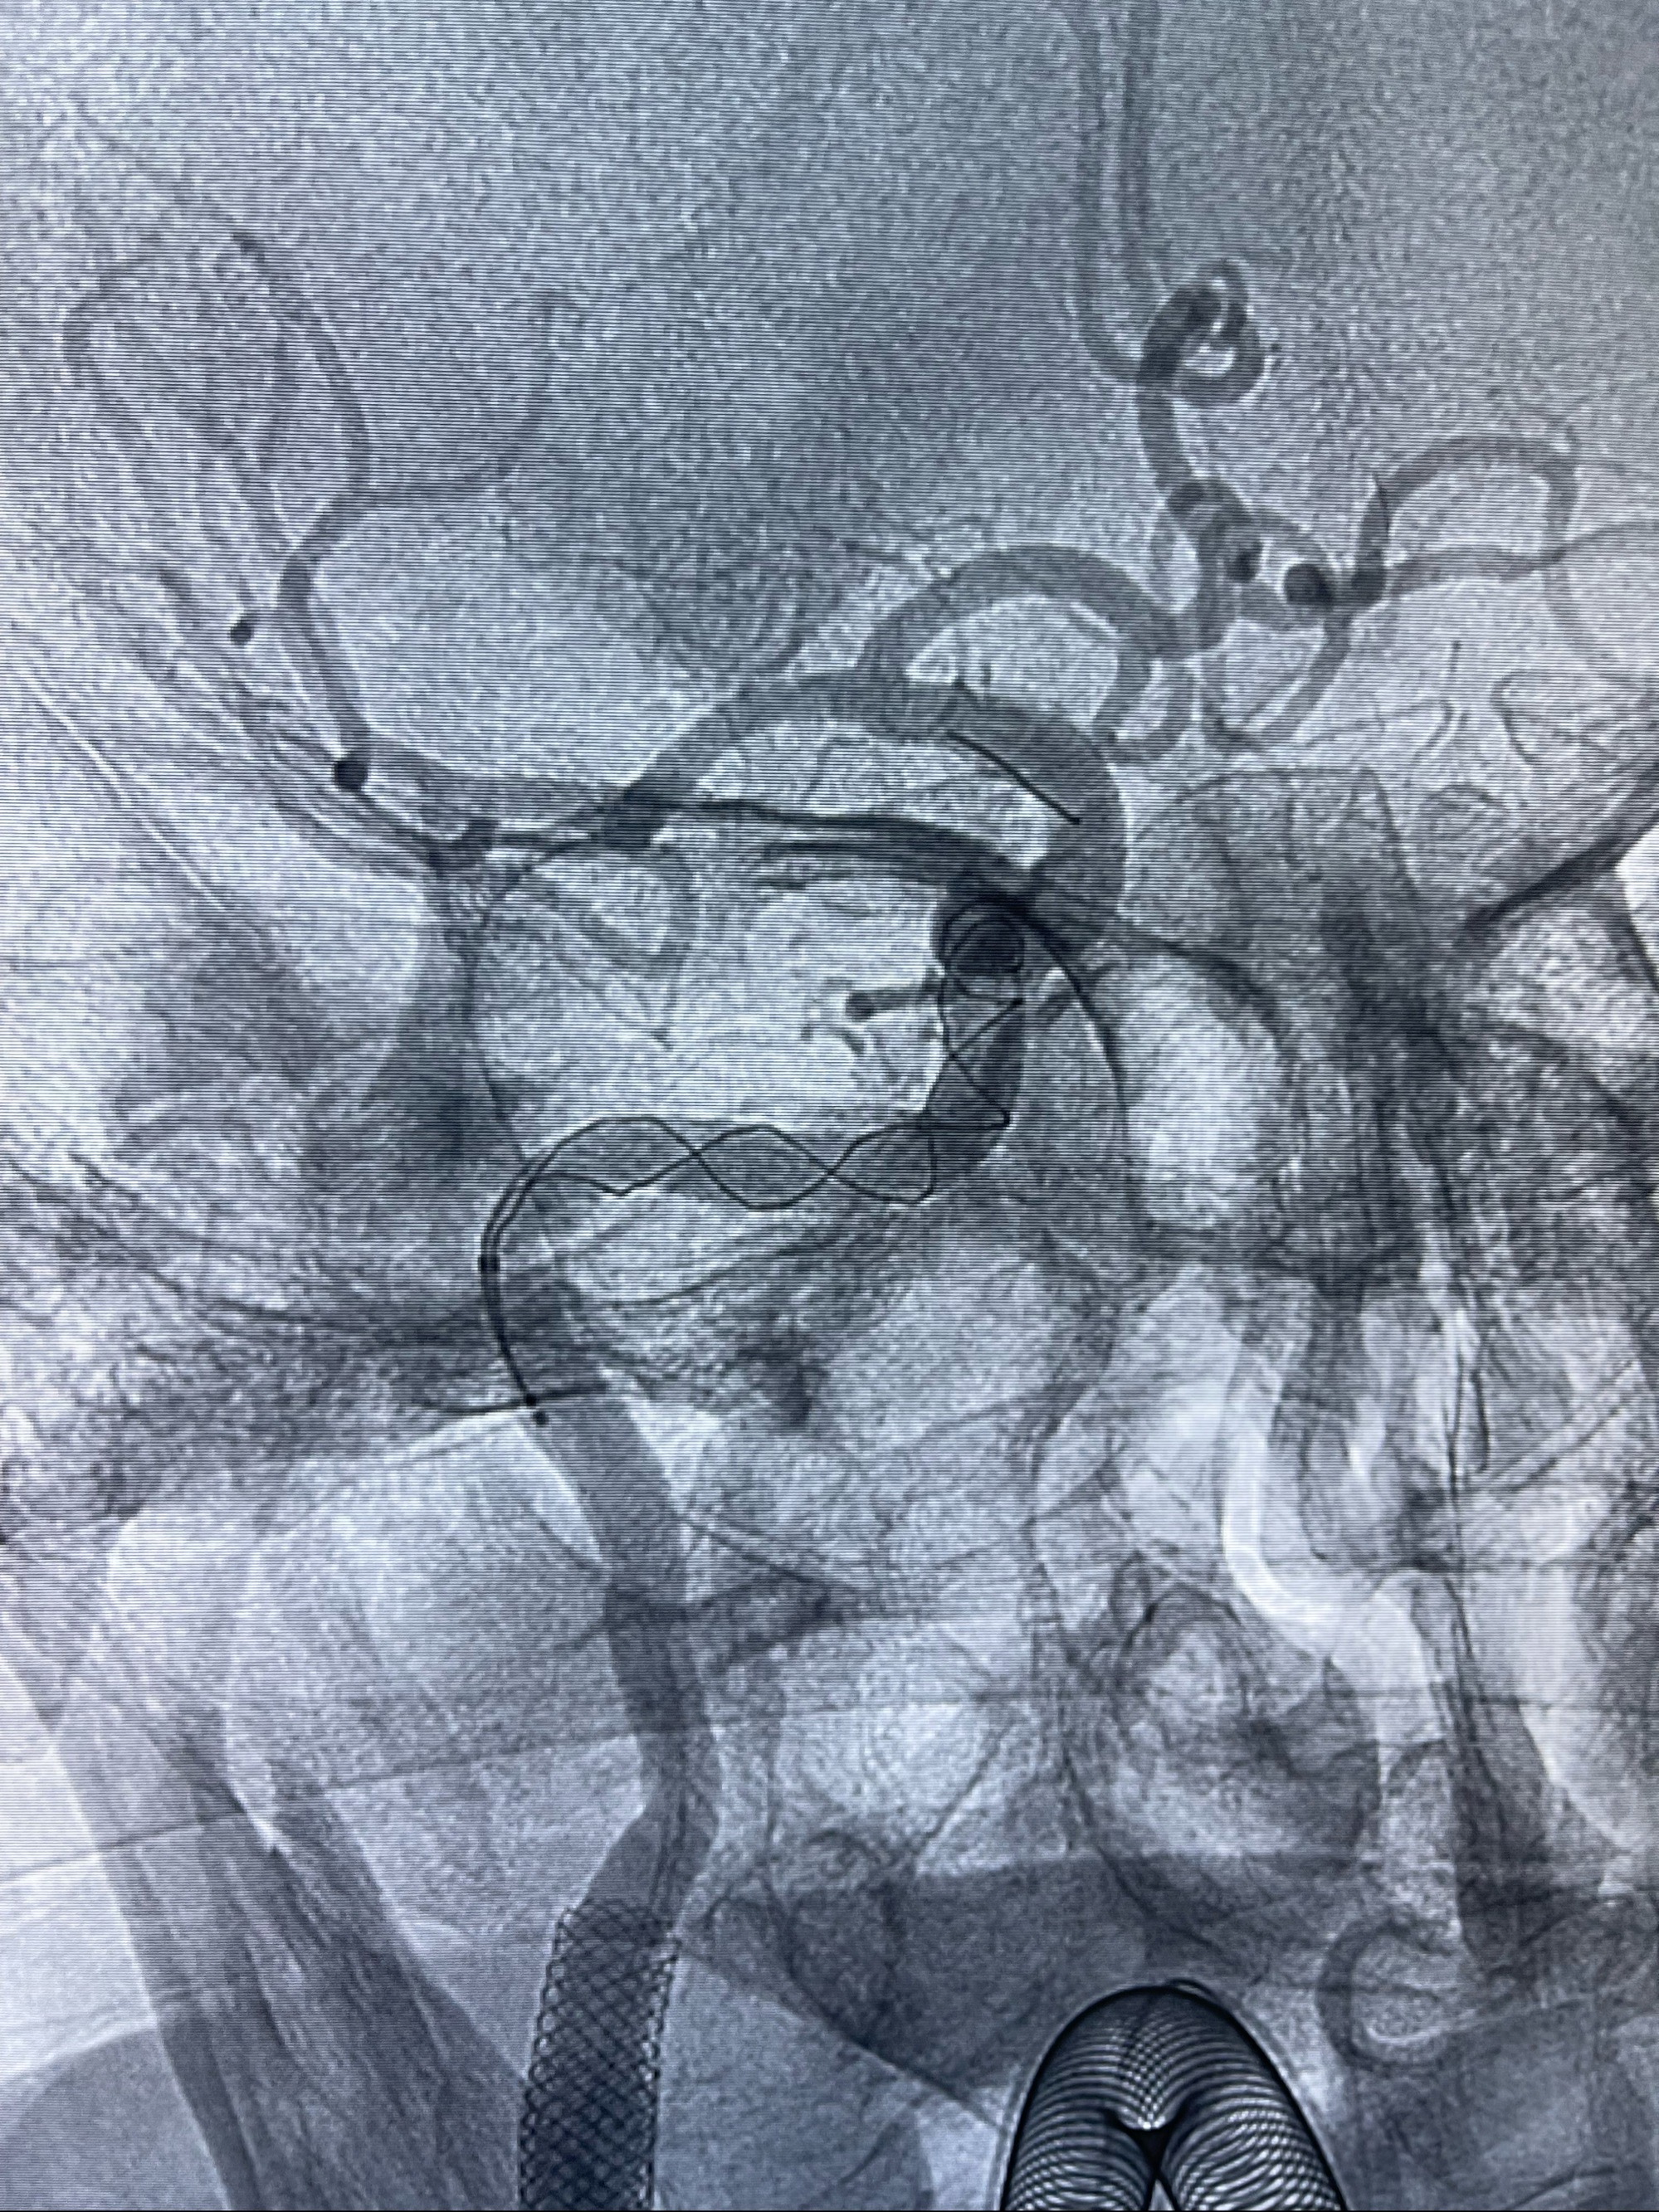

路径图下4-20mm球囊在导丝引导下超选择性至狭窄段,以6-8个大气压扩张,持续30s

泄除球囊造影显示局部管腔扩张佳

后移球囊至颈段狭窄段,以8-12个大气压扩张,持续30s后泄除球囊

即刻造影显示狭窄扩张佳

重新行“路径图”,支架导管在微导丝引导下超选择性插入至右侧颈内动脉眼段,4.5-50mmLeo支架释放,远心端位于海绵窦段,近心端位于岩骨段狭窄段以近

即刻造影显示支架贴壁佳

路径图下,5.5-50mmLeo支架导管在微导丝引导下超选择性插入远段Leo支架内

两枚支架部分重叠

多次确认支架位置及打开贴壁情况

支架完全打开,近心端位于原颈动脉支架远心端内